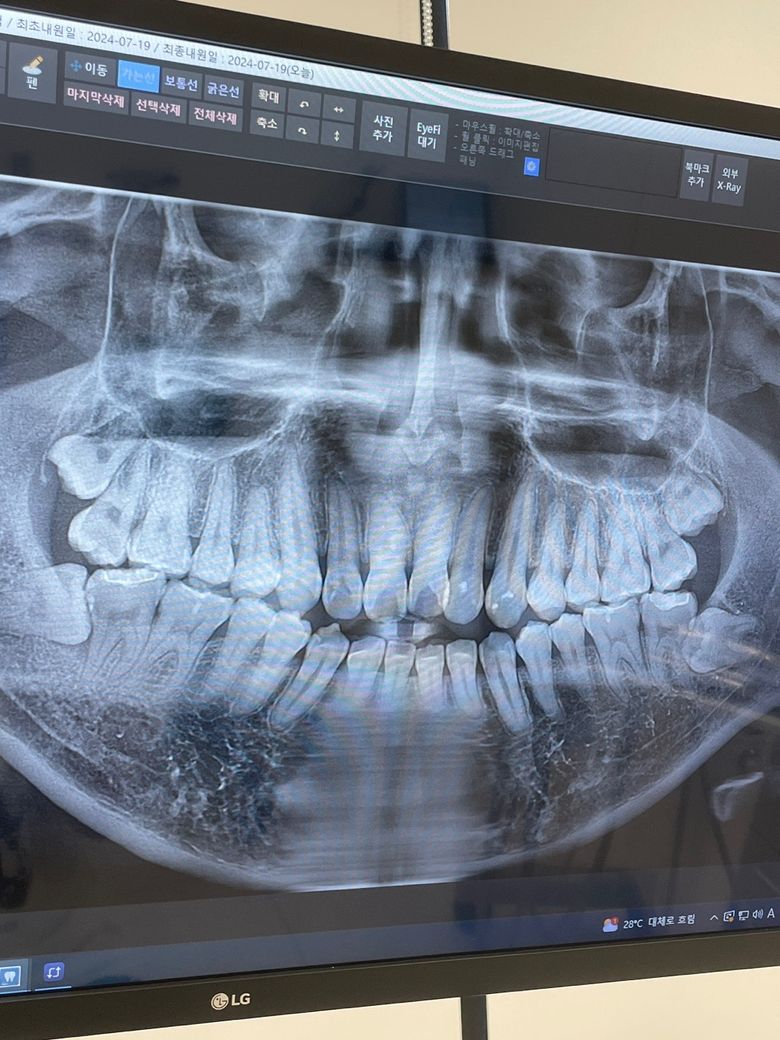

이정도 사랑니면 회복이 얼마나 걸릴까요??

군대가기 35일정도 남았는데 사랑니를 빼고 가는게 좋을거 같긴 한데..막상 사랑니때문에 신경쓰여서 입대 전에 그냥 앓다만 갈거같아서 고민되어 올려봅니다 입대 후에 빼는건 추천하지 않으실까요?

현재 매복된 사랑니가 있어 방치시에 앞의 어금니를 상하게 할수 있기에 가능한 빨리 발치하는 것이 필요로 되기에 입대전에 발치를 하고 입대를 하길 권합니다.